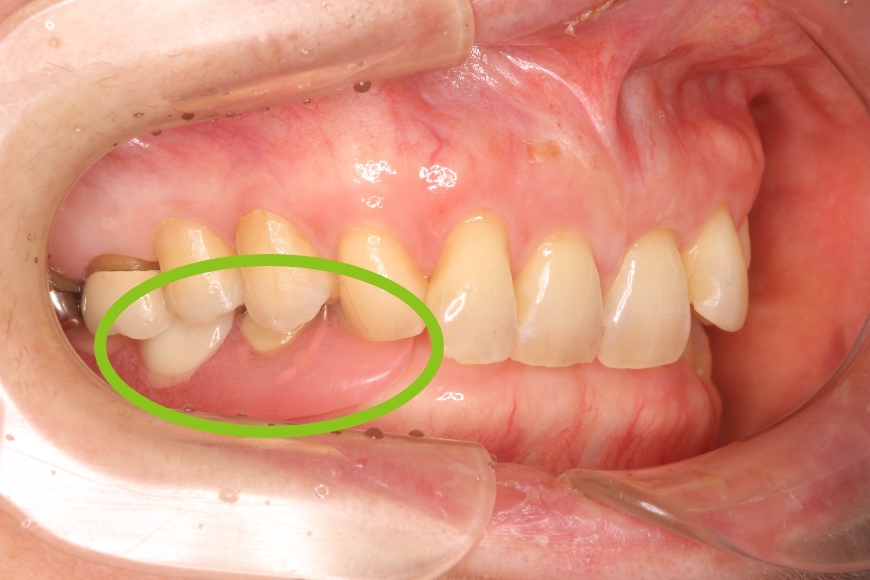

セレーブデンチャー(金属のばねが無い入れ歯)

60歳女性。ばねが目立たない入れ歯を作りたい。

治療前①

治療後①

治療前②

治療後②

治療内容 今までは入れ歯のばねが金属だったため、見た目が気になり大きな口を開けて話す事ができないので、入れ歯を作り変えてほしいとのことで来院されました。

相談した結果、金属のばねが無い入れ歯を作り直すことになりました。

治療期間 1カ月

治療費用(総額)

242,000

(治療時の金額であり、時期や手法により異なる場合があります。)

副作用・リスク ・保険適用外の入れ歯となります。

・薄くて軽く、また割れにくい素材ですが、割れないわけではありません。義歯の修理の際は、預かり修理が必要なこともあります。